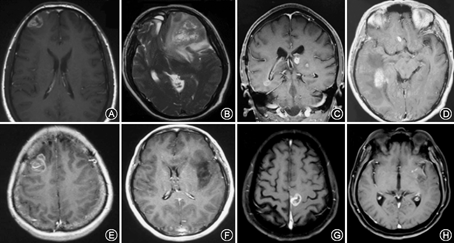

患者男,38岁,因发作性肢体抽搐1周入院。体格检查:无明显阳性体征。入院行头颅增强MRI示右侧额叶团块状长T1长T2异常信号,增强扫描呈明显不均匀环形强化(图1A),考虑为颅内肿瘤,行右额叶肿瘤全切除,术后病理学诊断:右额叶间变型星形胶质细胞瘤合并局灶胶质母细胞瘤(WHOⅣ)。术后予放疗及替莫唑胺同步及辅助化疗12个疗程。术后2年因头痛再次就诊,增强MRI见左额叶类圆形长T1长T2异常信号影,有明显不均匀强化,胼胝体无累及(图1B)。再次行左额叶肿瘤大部切除。术后病理学为胶质母细胞瘤(WHO Ⅳ级),术后予替莫唑胺节律方案(7 d/7 d)化疗+贝伐单抗靶向治疗,共4个疗程,但复查显示肿瘤仍持续进展,疾病进展后6个月时患者死亡,总体生存期30个月。

患者男,56岁,因右侧偏身感觉障碍伴右侧肢体乏力半年余入院。体格检查:右侧触觉、痛觉、温觉、本体感觉减退明显,右侧肢体肌力3级,右Babinski征阳性。MRI示左侧丘脑及右侧颞叶深部分别见团块状长T1长T2信号影,右颞叶病灶有强化,左侧丘脑病灶无强化(图1C)。入院前曾于外院接受针对左侧丘脑病变的三维适形分割放疗及替莫唑胺(TMZ 75 mg/m2)同步化疗,但右颞叶病变未行放射治疗。入院后行右颞叶肿瘤切除术,术中进行了肿瘤全切术。病理学为胶质母细胞瘤(WHO Ⅳ级),分子检测IDH1/2(–),MGMT启动子甲基化(–),1p19q杂合子突变(–)。术后患者接受针对右颞叶术区再次放疗和ACNU化疗。术后6个月复查MRI肿瘤进展,左侧丘脑和右侧脑室三角部出现多发增强灶,于术后8个月死亡,总体生存时间为14个月。

患者男,58岁,因头晕2年,加重伴头痛、恶心呕吐0.5个月入院。体格检查:理解力轻度下降,四肢肌力、肌张力正常,病理症阴性。MRI见右侧脑室三角部脑室旁和右额叶片状水肿,中线移位,增强见右颞叶片状不规则增强影(大小5.4 cm×3.4 cm×3.8 cm)、右侧额叶增强后见多个强化结节影(图1D)。行右颞叶肿瘤切除近全切除,术后病理学为胶质母细胞瘤(WHO Ⅳ级),术后患者症状短期改善,随后加重并出现意识障碍,1个月时复查即见术区肿瘤复发,而且右额多发病灶也进一步进展。行多发病灶的放疗和替莫唑胺同步化疗,同时给予贝伐单抗治疗脑水肿,患者意识逐渐清醒,症状显著好转,术后6个月随访患者仍然生存,KPS评分90分。